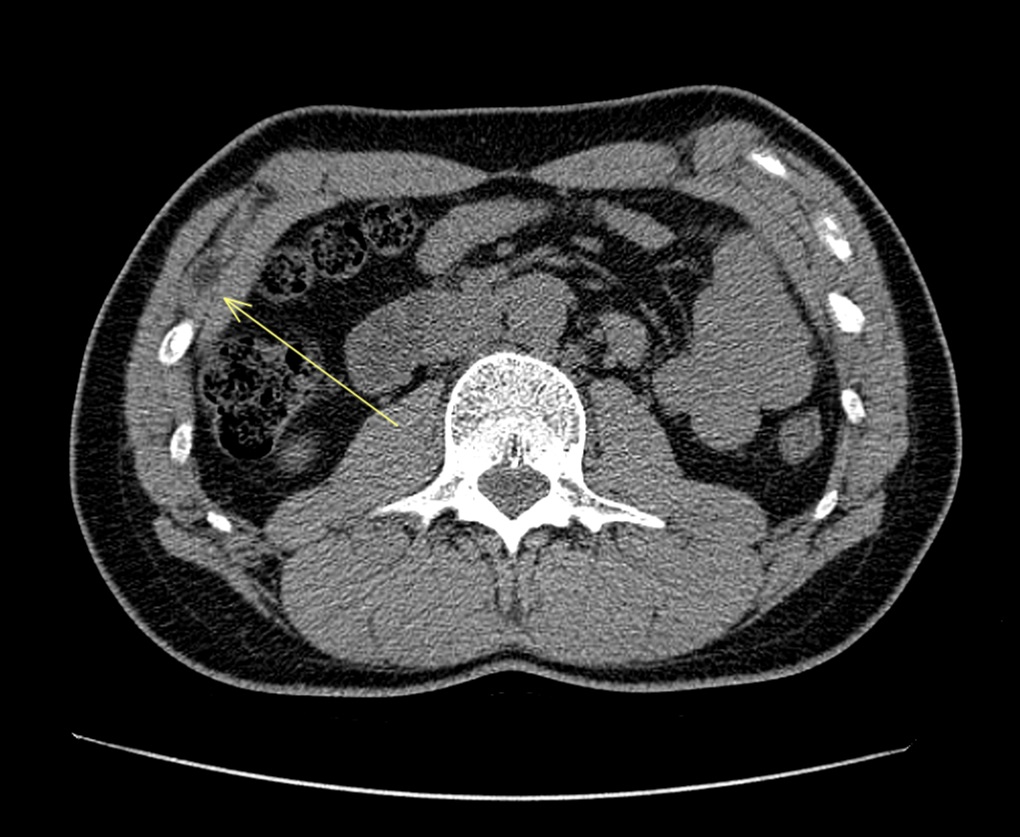

L'instabilità delle giunture costali può portare allo scivolamento delle punte libere delle coste inferiori (Figure 1-2), causando dolore e irritazione dei tessuti circostanti (Figura 3), in particolare del nervo intercostale corrispondente o dei fasci muscolari/tessuti molli adiacenti, generando una condizione di dolore toracico cronico; solitamente la X costa è quella più colpita.

Tc Torace-addome che mostra zona di conflitto con flogosi tissutale in corrispondenza della X costa di destra (Freccia)

Tuttavia, a causa della somiglianza dei sintomi con altre condizioni toraciche, possono essere necessari esami di imaging come radiografie, ecografie, TC o risonanze magnetiche. Le indagini radiologiche mostrano in genere reperti minimamente patologici e non sono dirimenti in senso diagnostico, bensì risultano più utili per escludere patologie sottostanti. La Tc Torace con ricostruzioni tridimensionali (Figure 1-3) può confermare il sospetto clinico ed indirizzare il trattamento.